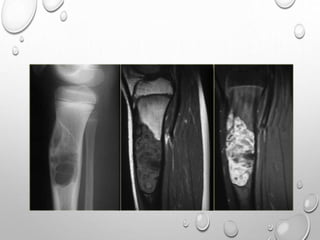

RADIOGRAPHS USUALLY DEMONSTRATE A PARTIALLY OSSIFIED, LOBULATED,

CARTILAGINOUS MASS ARISING UNILATERALLY FROM THE AFFECTED

EPIPHYSIS WITH OR WITHOUT AN OSSEOUS CONNECTION. THE DIAGNOSIS

IS USUALLY MADE WITH RADIOGRAPHS, BUT THE LESION CAN BE MISTAKEN

FOR AN INTRA-ARTICULAR LOOSE BODY, OSTEOCHONDROMATOSIS, OR

SYNOVIAL CHONDROMATOSIS.

CT CAN HELP DEFINE THE ANATOMIC RELATIONSHIP BETWEEN THE MASS AND

THE HOST BONE, AND MRI CAN SHOW THE EXTENT OF EPIPHYSEAL

INVOLVEMENT AND JOINT DEFORMITY AND THE STATUS OF THE ARTICULAR

SURFACE.

THERE MAY BE A CLEAVAGE PLANE DEMONSTRATED BETWEEN THE LESION

AND HOST BONE THAT GRADUALLY OSSIFIES AS THE LESION MATURES